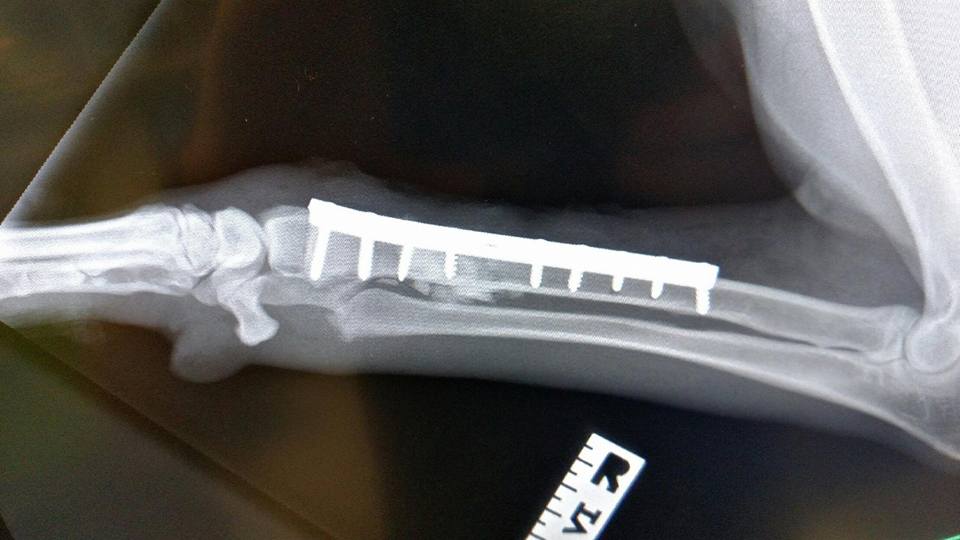

Here's an X-ray showing all the screws in place that will support the bone while the break heals. Looks like Doc was as perfect as always.

The Surgeon had to find The breaks and plan for the best way to put me back together.  I'm still growing so this has to be done in a way that does not impede my bones ability to grow normally.